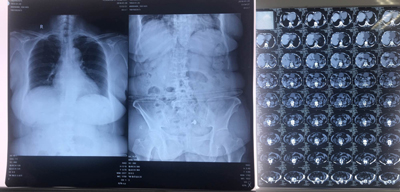

64岁的陶女士,因右肾积水、右侧输尿管上段结石入住我院泌尿外科。于元月24日下午两点半,连硬外麻下行右侧输尿管软镜钬激光碎石术,手术历时1小时,术后第一天就可以下床活动,恢复快。

患者影像学资料